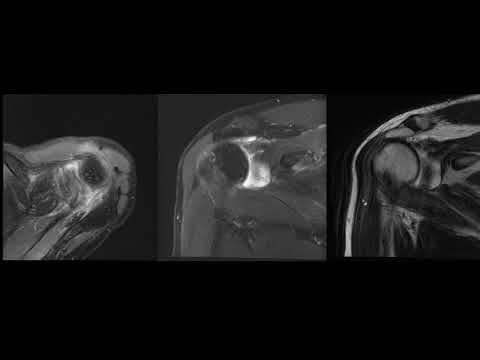

МРТ Плечевого сустава. Норма.

Подробный анализ МРТ плечевого сустава

Разбор МРТ. Случай с ПЛБС.